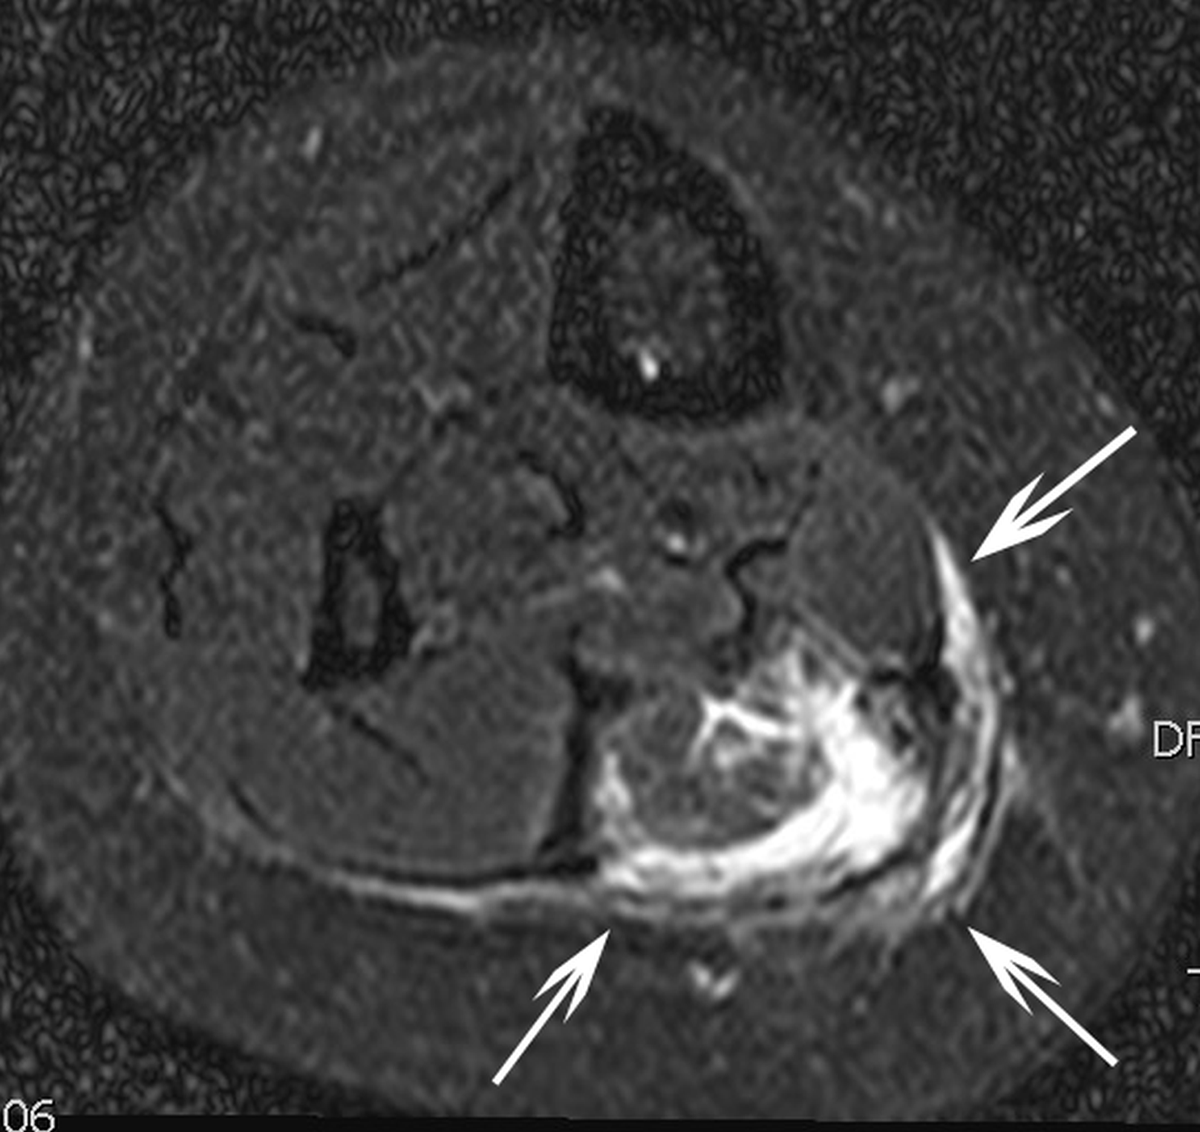

Clinical follow-up at 1 and 6 months revealed complete resolution of the swelling symptoms in all patients; resolution of pain was observed in three out of four patients and less invalidating pain in the remaining patient as summarized in Table 2. One patient presented with new onset of partial loss of muscle strength over the first six months after the index RFA. Radiological re-evaluation with magnetic resonance imaging, performed three months after RFA, demonstrated in this patient complete disappearance of the ablated VM (Figure 1b).

Figure 1b

T2-weigthed axial magnetic resonance image in the same patient three months after percutaneous radiofrequency ablation which was performed after two failed percutaneous sclerotherapies with sotradecol. Hyperintense rim (white arrows) around the ablated area suggestive for perileasional oedema.